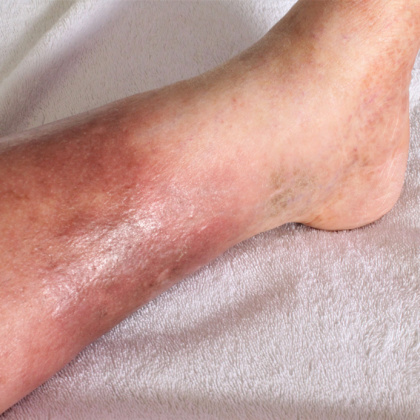

Product Item: Cellulitis leg clearance

Cellulitis leg clearance